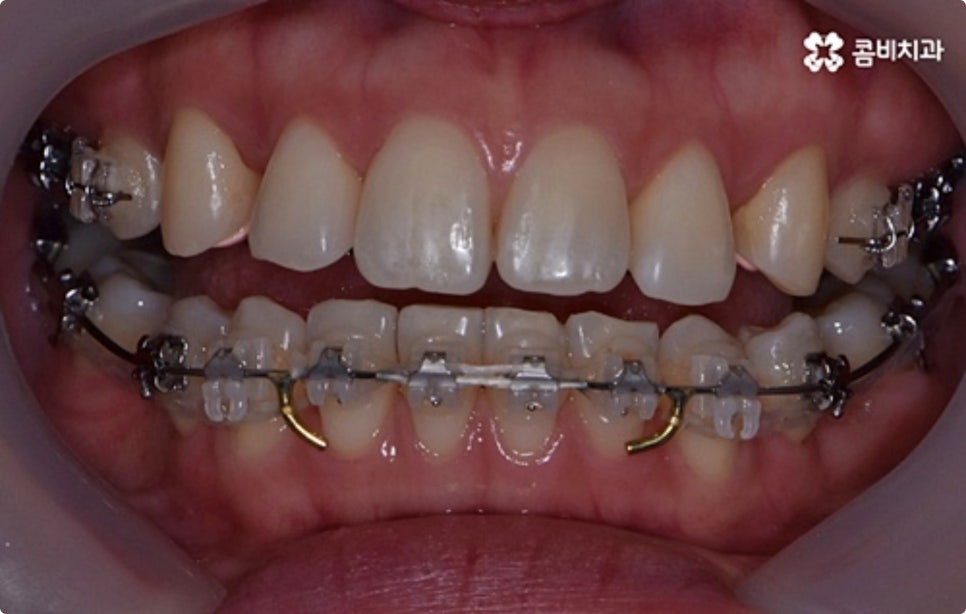

클리피씨 교정도 치아 색상의 세라믹 재질을 사용하기 때문에 심미성이 높은 편이지만 만약에 장치가 아예 겉으로 드러나지 않았으면 좋겠다고 생각하신다면 브라켓을 치아 안쪽에 부착하는 설측교정을 이용할 수 있는데요. 하지만 설측교정은 혀와 맞닿는 부분의 이물감, 통증, 발음상 문제 등을 일으킬 수 있기 때문에 잘 보이는 윗니는 설측으로, 잘 드러나지 않는 아랫니는 보통 교정과 같이 순측 (입술쪽) 으로 진행하는 콤비교정을 통해 이를 보완할 수 있어요. 사진에서 살펴보실 수 있는 케이스 역시 이렇게 콤비로 진행한 직장인치아교정 과정으로 시간이 지날수록 점차 치열이 가지런해지고 교합이 올바르게 개선되는 것을 확인해 보실 수 있습니다.